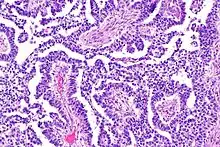

A micrograph of the primitive neuroepithelium of an immature teratoma, showing encapsulated mass.[6]

Teratoma are most common germ cell tumor of ovary. Teratomas can be divided into two types: mature teratoma (benign) and immature teratoma (malignant). Immature teratomas contain immature or embryonic tissue which significantly differentiates them from mature teratomas as they carry dermoid cysts.[7] It is commonly observed in 15 to 19-year-old women and rarely in women after menopause.[8] Immature teratomas are characterized with a diameter of 14–25 cm, encapsulated mass, cystic areas, and occasional appearance of hemorrhagic areas.[9] The stage of immature teratomas is determined depending on the amount of immature neuroepithelium tissue detected.[7]